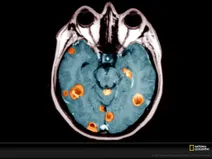

The genetic underpinnings of cancer are diverse and many types of genomic aberration — from single nucleotide variants (SNVs) to structural variants (SVs), copy number variants (CNVs), fusion transcripts, and epigenetic modifications (e.g. DNA/RNA methylation) — can cause, contribute to, or indicate disease. As a result, researchers traditionally relied on multiple techniques to identify and analyse different facets of cancer.

Now, with Oxford Nanopore technology, researchers are going beyond next-generation sequencing (NGS), generating sequencing reads of any length, including ultra-long reads (>4 Mb achieved) that can span complex genomic regions. This, combined with integrated base modification detection and real-time results, means that nanopore oncology sequencing delivers a streamlined and rapid solution for complete characterisation of cancer and tumour samples.